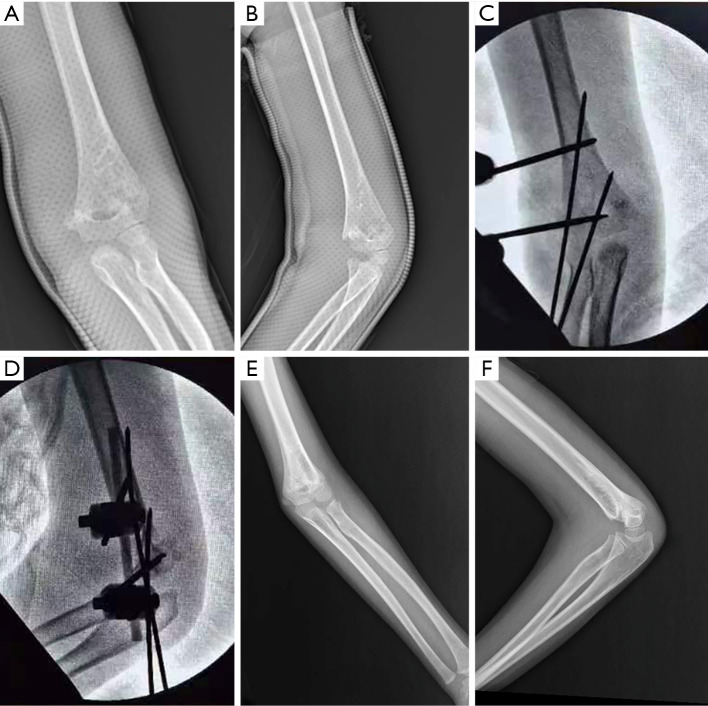

Background: Medial comminuted supracondylar humeral fracture (SCHF) is a common elbow injury in children, and there is no consensus on treatment yet. While crossed pinning offers biomechanical advantages for medial comminution, it carries inherent risks of iatrogenic ulnar nerve injury. This study aims to describe the surgical technique of lateral external fixation (LEF) combined with K-wire (KW) as an alternative technique and evaluate the clinical and radiological outcomes of this method.

Methods: We retrospectively analyzed 53 children (mean age 7.1 years; 28 males, 25 females) with Gartland type II (n=9) and III (n=44) SCHFs with medial comminution, treated between January 2019 and January 2022. All fractures were fixed with LEF and KW. Functional outcomes were assessed using Flynn's criteria, with radiological parameters (carrying-angle loss, shaft condylar angle, Baumann's angle) measured at a minimum 12-month follow-up (range, 12-26 months).

Results: At last follow-up, radiographic evaluation demonstrated a mean shaft condylar angle of 37.1°±4.4°, Baumann's angle of 75.6°±3.6°, and carrying angle loss of 3.4°±2.0°. Range-of-motion loss averaged 3.5°±2.4°. According to Flynn's criteria, 87% (46/53) achieved excellent and 13% (7/53) good outcomes. Subgroup analysis revealed significantly greater carrying-angle deviation (P<0.01) and motion loss (P=0.05) in Gartland III versus II fractures. Complications included two superficial pin-site infections (3.8%) resolved with oral antibiotics; no instances of iatrogenic nerve injury, vascular compromise, or malunion occurred.

Conclusions: For pediatric SCHF with medial comminution, external fixator (EF) plus KW is a feasible alternative without the risk of iatrogenic ulnar nerve injury.